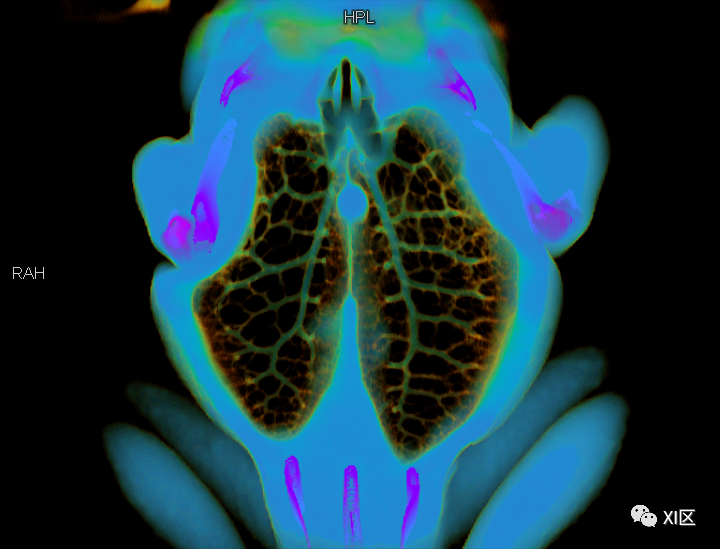

牛蛙三维重建,肺几乎占了整个胸腹腔

首先,

我们看一下牛蛙的肺

这只牛蛙的肺体积非常大

测量发现

体积为38.41ml

之前我们知道了这只牛蛙的总体积

简单计算后发现

牛蛙的肺占全身体积的

13.14%

牛蛙志愿者的肺部CT为38.41ml

作为对比,正常体型的成年人

平静状态下

肺部体积约为全身体积的4%左右

可以说

牛蛙的肺比人大3倍以上